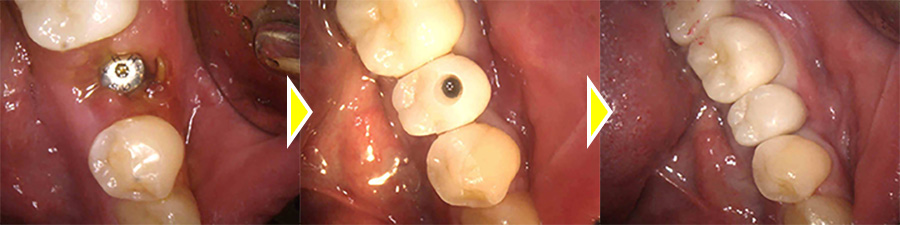

インプラント治療の実施

一度被せ物を除去し、中身の状態を確認したところ、歯の根っこに破折線が見られたため、患者様のご希望で、抜歯、インプラントを行うことになりました。

歯が破折していることにより、膿が大きく骨欠損が多かったため、インプラントの持ちを良くするために骨造成も同時に行っています。

上部構造(人工歯)の装着・治療完了

術後は奥歯で硬いものもしっかりと噛むことができるようになり、審美的にも機能的にも大変満足していただいています。

現在は定期的なクリーニングに通院していただき、キレイな状態を保っていただいています。